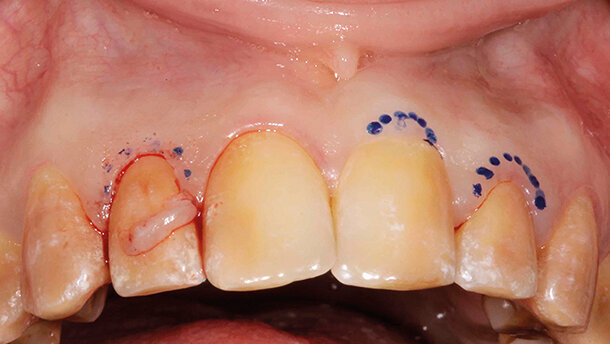

Prima della terapia definitiva sono state eseguite delle correzioni chirurgiche dei settori posteriori per azzerare difetti parodontali ossei (Figg. 2a, 2b) o ridurre l’alterata eruzione passiva (Figg. 2c, 2d). Una volta ottenuta la guarigione dei settori posteriori (Figg. 3a, 3b), sono state eseguite delle correzioni estetiche del settore frontale (Fig. 4).